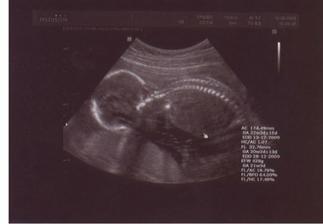

12.8.09 - velký UTZ v 21tt - mimi váží 428g, vše OK a je to HOLČIČKA :o)

20.10.09 - velký UTZ v 30tt, vše je OK, holčička váží 1825g, je stále hlavičkou dolů